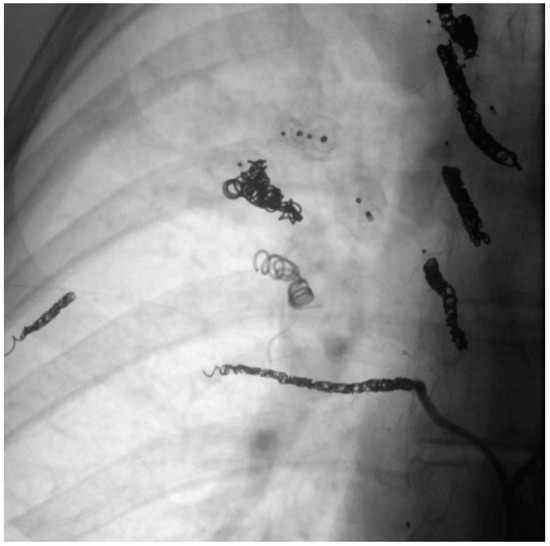

When assessing the implanted embolization material, it was also noticed that some of the coils in the DSA appeared thinner than others. Figure 11 shows a Nester® Embolization Coil from Cook Medical, which is available in a thickness of 0.035 inch and is regularly used in our department. In ten patients with a total of 29 recanalized AV shunts, the implanted coils appeared thinner than those used at our department, with these accounting for 45.3% of the total number of recanalized AV shunts. An example is therefore shown in Figure 12. In this context, a possible correlation between the use of coils with a lower thickness and a possible increased recanalization rate after embolization was discussed.

Figure 12. Coils of a patient with external treatment and which appear thinner than the Nester® Embolization Coil.